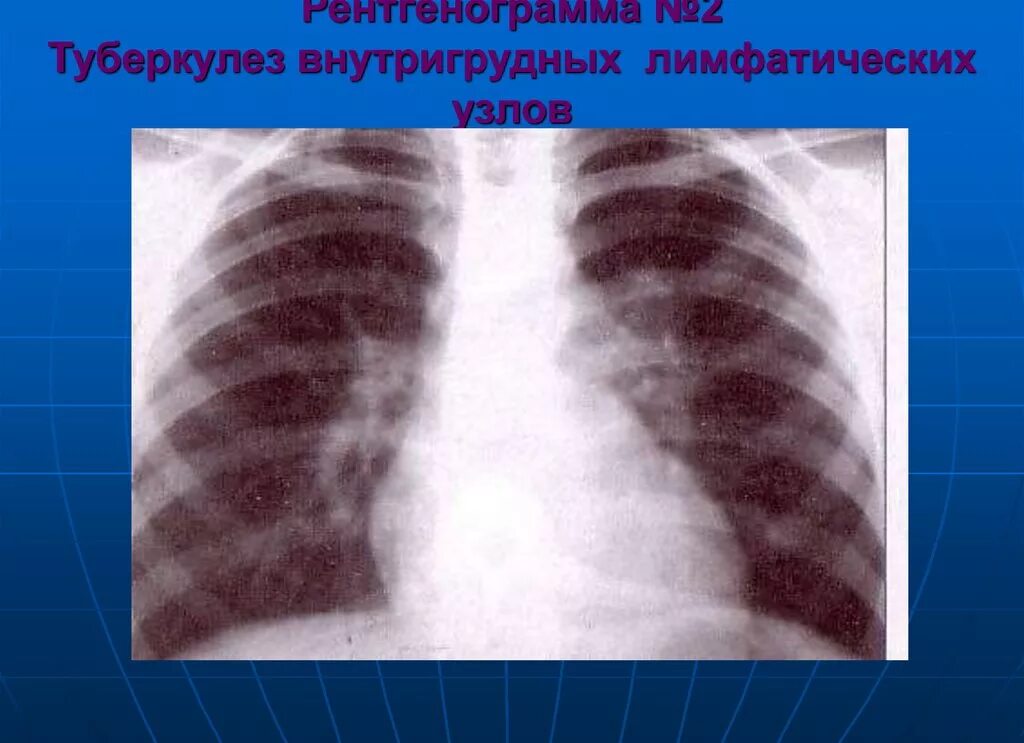

Бронхоаденит это